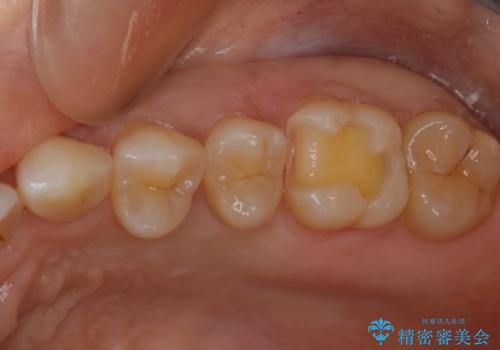

大臼歯 大きな虫歯をセラミックインレーに

- 歯が黒くなってきているのが気になるとのことで、レントゲンを撮影し診断を行いました。

幸い神経までは到達していない虫歯だったため、部分的な詰め物「インレー」で治療を行うこととなりました。

歯の一部が虫歯になってしまった場合の治療法のひとつにインレーがあります。

虫歯になってしまった部分を含めて詰め物用に形を削り整え、型取りをし、出来上がってきた技工物をセメントで接着します。